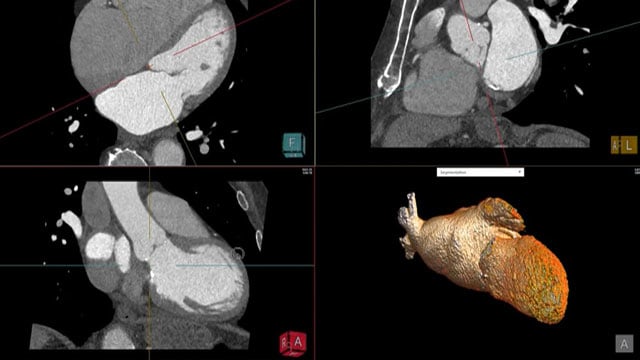

Contemporary imaging trends in aortic stenosis - How to diagnose

10 Mar 2023 – From PCR Imaging Valves Madrid 2023

Watch these presentation to know all about the latest diagnostic tools in aortic stenosis, to learn how to use 3D in aortic stenosis and to understand when 3D echo and exercise echo are useful.

Imaging before and after TAVI - How to treat

Consult this session on imaging before and after TAVI to learn how to better select patients for TAVI, to understand how to treat paravalvular leak and to know how to deal with and prevent valve thrombosis.